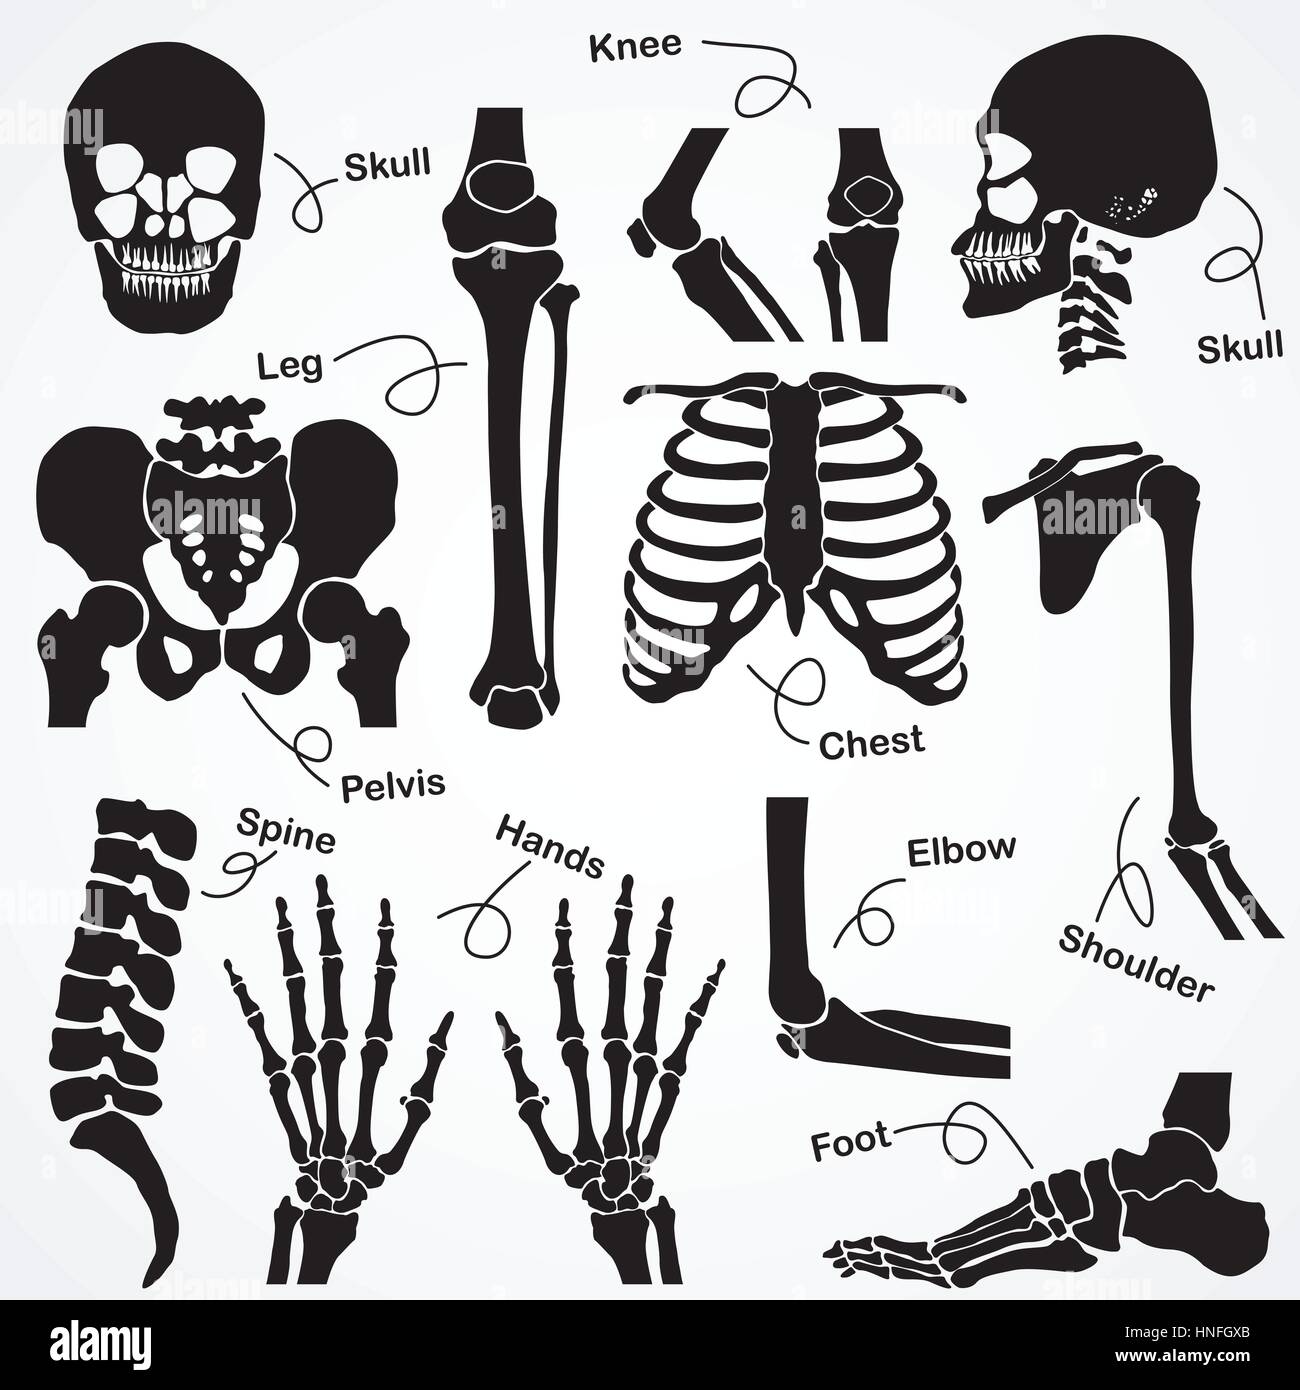

Collection du squelette (crâne, colonne vertébrale, du cou,Genou,joints,vente,poignet,dos,bras avant-bras,COUDE,foot,jambe Cheville,cuisse,hip,,pelvienne,thorax,nervure, clavicule,sh Illustration de Vecteurhttps://www.alamyimages.fr/image-license-details/?v=1https://www.alamyimages.fr/photo-image-collection-du-squelette-crane-colonne-vertebrale-du-cou-genou-joints-vente-poignet-dos-bras-avant-bras-coude-foot-jambe-cheville-cuisse-hip-pelvienne-thorax-nervure-clavicule-sh-133722915.html

Collection du squelette (crâne, colonne vertébrale, du cou,Genou,joints,vente,poignet,dos,bras avant-bras,COUDE,foot,jambe Cheville,cuisse,hip,,pelvienne,thorax,nervure, clavicule,sh Illustration de Vecteurhttps://www.alamyimages.fr/image-license-details/?v=1https://www.alamyimages.fr/photo-image-collection-du-squelette-crane-colonne-vertebrale-du-cou-genou-joints-vente-poignet-dos-bras-avant-bras-coude-foot-jambe-cheville-cuisse-hip-pelvienne-thorax-nervure-clavicule-sh-133722915.htmlRFHNFGXB–Collection du squelette (crâne, colonne vertébrale, du cou,Genou,joints,vente,poignet,dos,bras avant-bras,COUDE,foot,jambe Cheville,cuisse,hip,,pelvienne,thorax,nervure, clavicule,sh